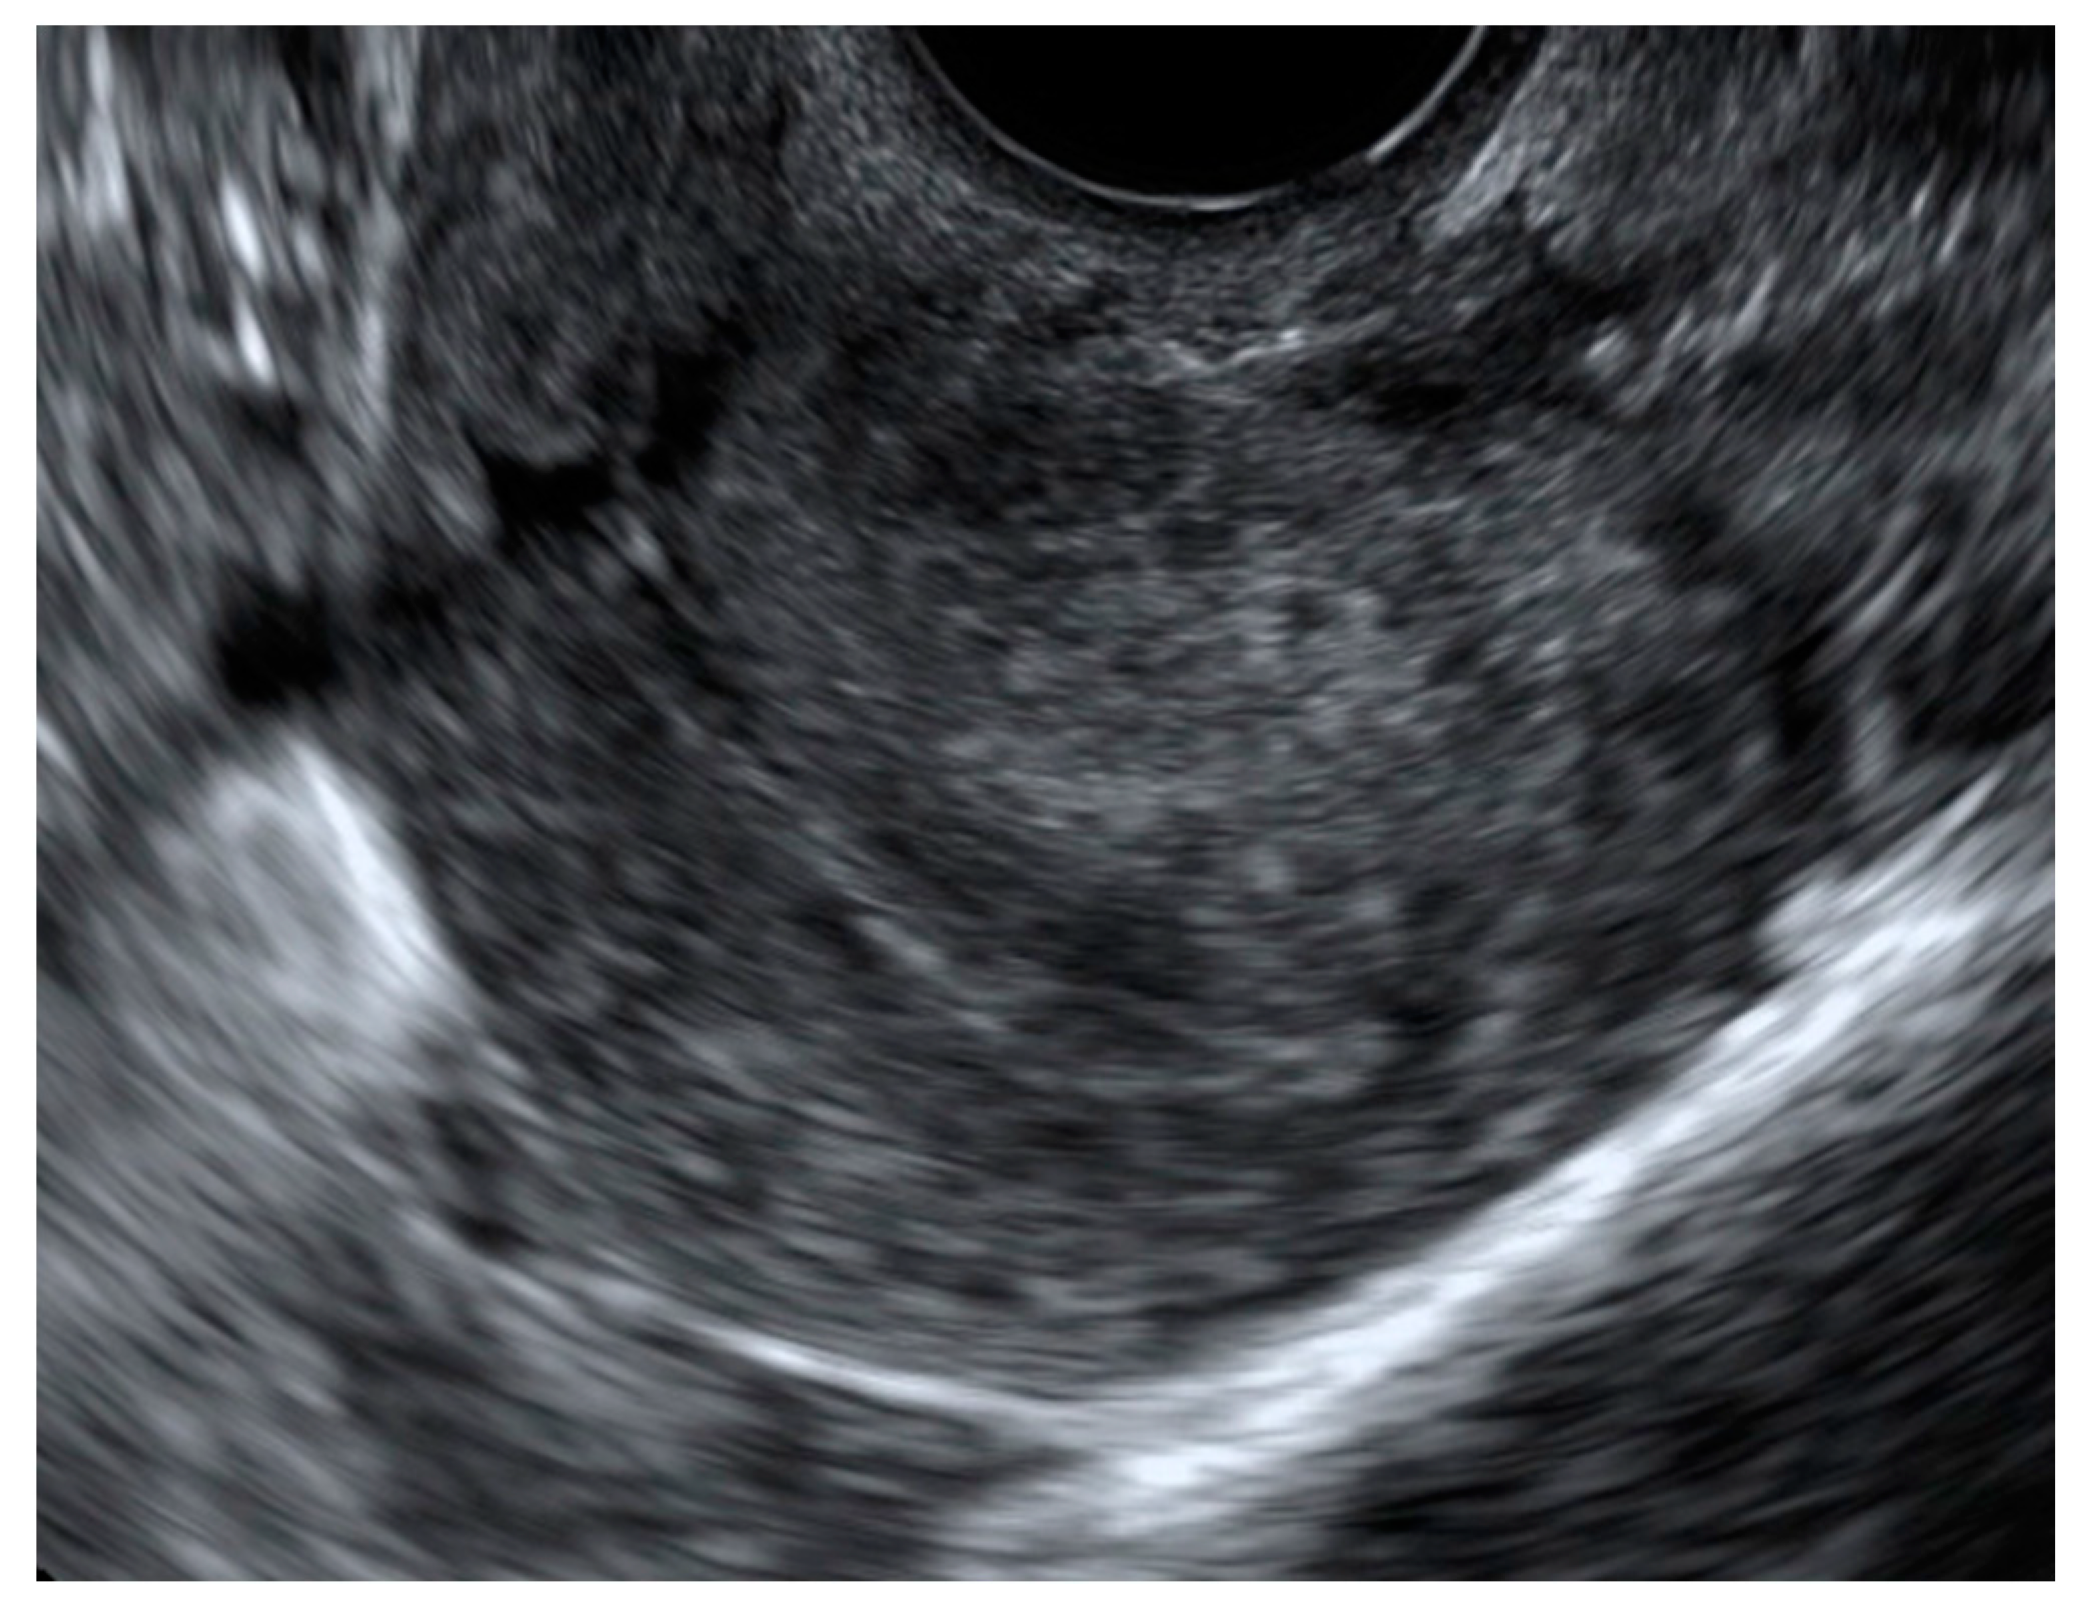

2.1. Ultrasound Diagnosis

- Myometrial cysts and intramyometrial cystic formations of any size (presence of a hyperechogenic halo is not mandatory). The contents could be anechoic, low-level, ground glass or of mixed echogenicity and may be surrounded by a hyperechogenic rim. Doppler can be used for differential diagnosis between blood vessels and myometrial cysts;

- Hyperechogenic islands with intramyometrial hyperechogenic areas within the myometrium that have no connection with the endometrium (regular, irregular, or ill-defined);

- Echogenic subendometrial lines and buds with hyperechogenic subendometrial lines or buds perpendicular to the endometrial cavity in a continuum with the endometrium, disrupting the junctional zone (JZ). On the other hand, the diagnosis of adenomyosis remains uncertain in cases of the presence of only indirect signs, including uterine wall asymmetry, translesional vascularity, JZ changes, fan-shaped shadowing, and globular uterus (Table 1).

- Irregular JZ with a poorly distinguishable endometrial–myometrial border;

- Disrupted JZ, possibly caused by focal or diffuse infiltration of the JZ by endometrial tissue. Uterine contractions may also give rise to apparent irregularities of the JZ or affect wall thickness;

- Alterations of the JZ due to subendometrial hyperechogenic lines and buds, ultrasound signs of focal adenomyosis infiltrating the JZ [26].